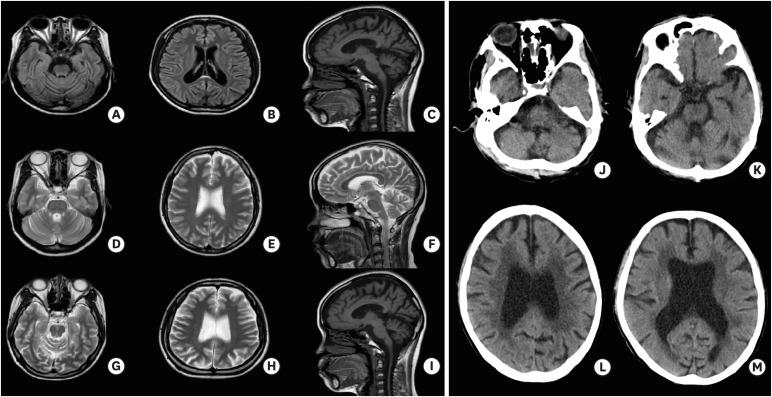

Dentatorubropallidoluysian atrophy (DRPLA) is a neurodegenerative disease caused by an expansion of a cytosine-adenine-guanine (CAG) repeat encoding a polyglutamine tract in the atrophin-1 protein. Unlike other CAG repeat diseases, sleep related problems have not been reported in patients with DRPLA. There was a 65-year-old man and his family with DRPLA. They suffered from seizure, gait disturbance, and cognitive decline. The patients commonly showed dream enacting sleep disorder, insomnia. The results from overnight polysomnography showed rapid eye movement (REM) without atonia in patients with DRPLA. The man died 2 years after diagnosis and was subjected for brain autopsy. We report REM sleep behavior disorders in patients with DRPLA confirmed with polysomnography with pathological description of the patient.

摘要

齿状核红核苍白球路易体萎缩症(DRPLA)是一种由抗萎缩蛋白 1 蛋白中编码多聚谷氨酰胺链的胞嘧啶-腺嘌呤-鸟嘌呤(CAG)重复扩增引起的神经退行性疾病。与其他 CAG 重复疾病不同,DRPLA 患者没有报告与睡眠相关的问题。本文报道了一例 65 岁男性及其家族的 DRPLA 病例。他们患有癫痫、步态障碍和认知能力下降。患者通常表现出梦动睡眠障碍和失眠。整夜多导睡眠图的结果显示,DRPLA 患者的快速眼动(REM)期间无动性。该患者在诊断后 2 年死亡,并接受了尸检。我们通过多导睡眠图检查并结合患者的病理描述,证实了 DRPLA 患者存在 REM 睡眠行为障碍。